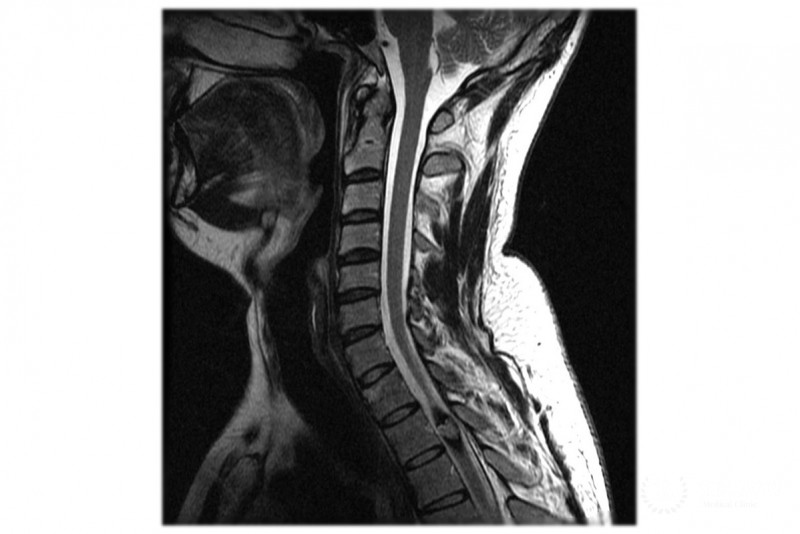

В нашем медицинском центре используется самое современное диагностическое оборудование. Одним из наиболее информативных методов диагностики каверномы является контрастное магнитно-резонансное исследование. Для наблюдения динамики изменений каверномы и прослеживания возможного возникновения новых каверном периодически проводится МРТ-обследование.

Как правило, при бессимптомных каверномах назначается контроль с помощью МРТ. Хирургия при бессимптомном течении данного заболевания является спорным вопросом. А при первичных кровоизлияниях из каверномы и неврологических симптомах хирургическое вмешательство является обязательным.